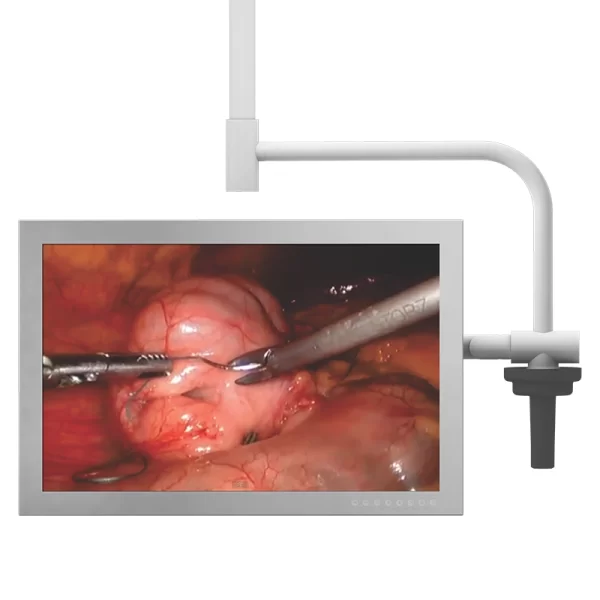

- Sistema “ENDO” que proporciona ao ambiente iluminação adequada para vídeo cirurgias, esta iluminação reduz a fadiga dos olhos durante os procedimentos endoscópicos e diminui o reflexo nos monitores LCD durante o procedimento e mantém o ambiente com iluminação suficiente para o trabalho.